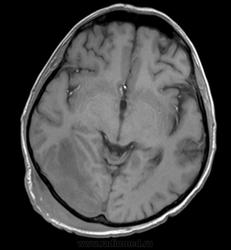

Мужчина проходит курс химиотерапии по поводу Т-клеточной лимфомы с первичным поражением кишечника (гистологическая верификация). За последний месяц - появление множественных очагов в печени, а также необычных изменений в голове.

- бесформенное образование в мягких тканях затылочной области, накапливающее контраст;

- утолщение твердой мозговой оболочки в той же области с накоплением контраста по пахименингиальному типу;

- отек прилежащей мозговой ткани с геморрагическими изменениями в коре, сопровождающийся масс-эффектом.

Мое мнение это лимфома кожи с прорастанием (если так можно сказать) через перфорирующие сосуды в ТМО, с кровоизлияниями в коре за счет повреждения сосудов. Либо это лептоменингальнаые проявления лимфомы. Больше на ум ние чего не приходит. Хотелось бы услышать мнение более опытных специалистов. но все почему-то молчат...

Я тоже думаю, что это лимфома. Думаю, не так важно, прорастает ли она из мягких тканей в мозговые оболочки, или наоборот. Только поражение мозговой оболочки - это пахи-, а не лептоменингиальные изменения.

В таком случае изменения в мозговой ткани - это отек, обусловленный нарушением венозного оттока по поверхностным венам; думаю, вкупе с геморрагическими изменениями этот отек можно квалифицировать как венозный инфаркт.

Учитывая явное снижение иммунитета больного, есть еще одна мысль - по поводу грибов. Я не уверен, могут ли грибы вызывать такие изменения, но чем черт не шутит?